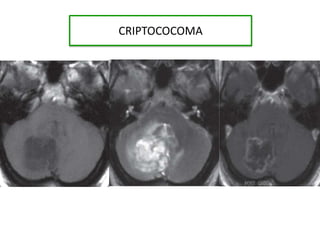

Imagenes “Soap bubble” Gangliosbasales Multiples focos hiperintensos bilaterales en ganglios basales . Pseudoquistes Hidrocefalia

• Hiperintensidad enlobulo derecho • Pseudoquistes bilaterales.

CRIPTOCOCOMA